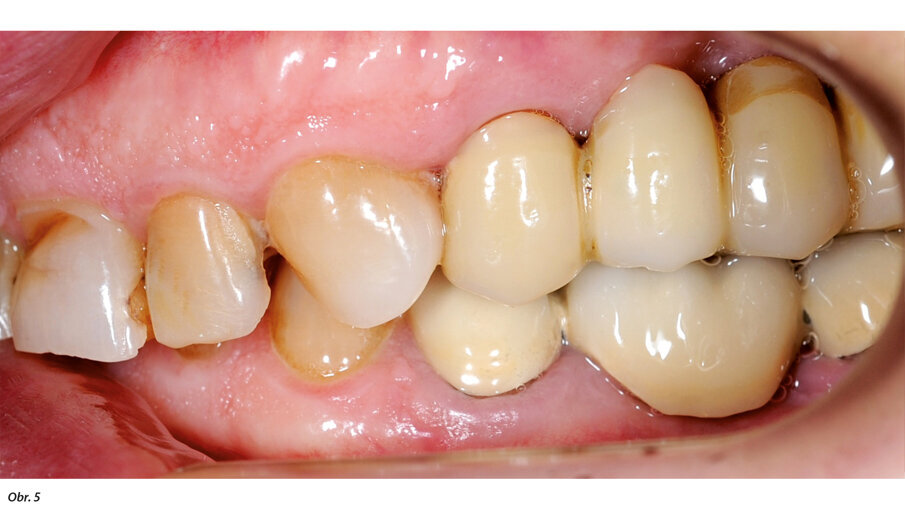

66letý pacient s non-inzulin dependentním diabetes mellitus a ischemickou chorobou srdeční se dostavil na ošetření parodontálního abscesu v oblasti radix relicta 12 a vícečetných fraktur stávajících náhrad (obr. 1–6). Během návštěvy byla zjištěna značná malokluze a ztráta VRO, abraze a fraktury stávajících náhrad i zbylých zubů a známky cervikální abfrakce. Pacient také trpěl mírnou bolestivostí svalů při palpaci, a to zejména v oblasti m. pterygoideus medialis et lateralis, sníženou schopností otevírání úst a slabými zvukovými fenomény v oblasti temporomandibulárních kloubů.